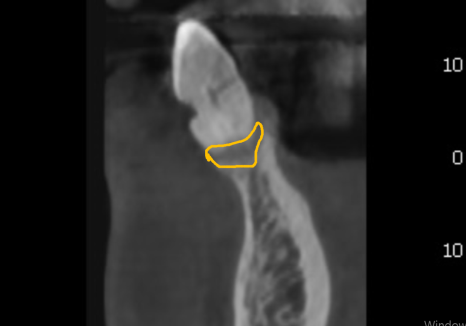

오랜 염증으로 잇몸뼈가 많이 내려가 있는 상태라,

일반적인 보철물을 올리면

치아가 비정상적으로 길어 보여

인상이 어색해질 우려가 컸는데요~

치아가 길어지지 않게

핑크 포세린(잇몸 색 도자기)으로

잇몸을 재현하여

260116

치아 길이가 짧아 보이도록

제작했습니다.

잇몸뼈가 많이 소실된 상황이었지만,

치아의 비율을 세심하게 조정한 덕분에 어색함 없이 아주 자연스러운 결과가 나왔습니다.^^